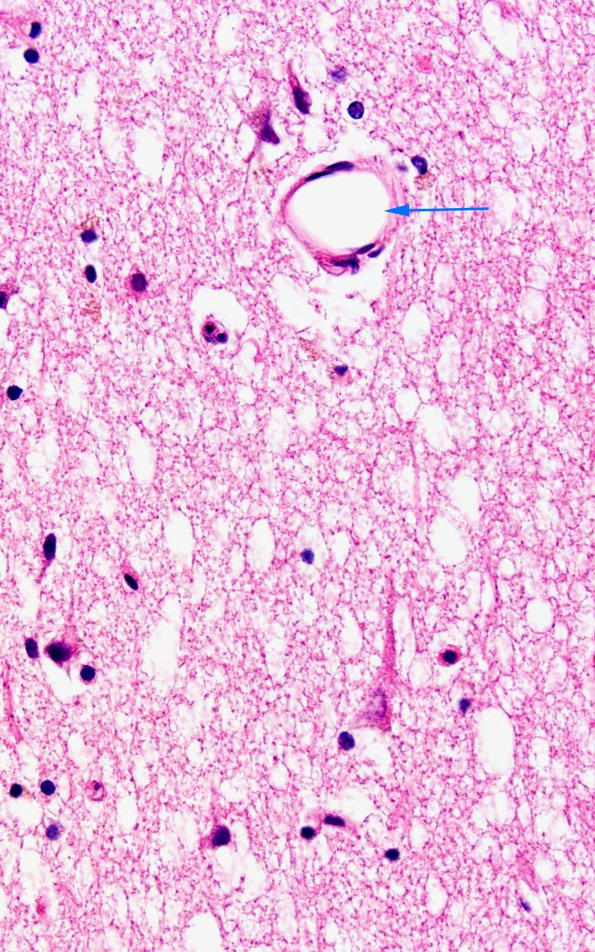

Higher magnification demonstrates pallor, edema, eosinophilic neuronal necrosis as well as an occluded vessel (1B6, arrow). (H&E)